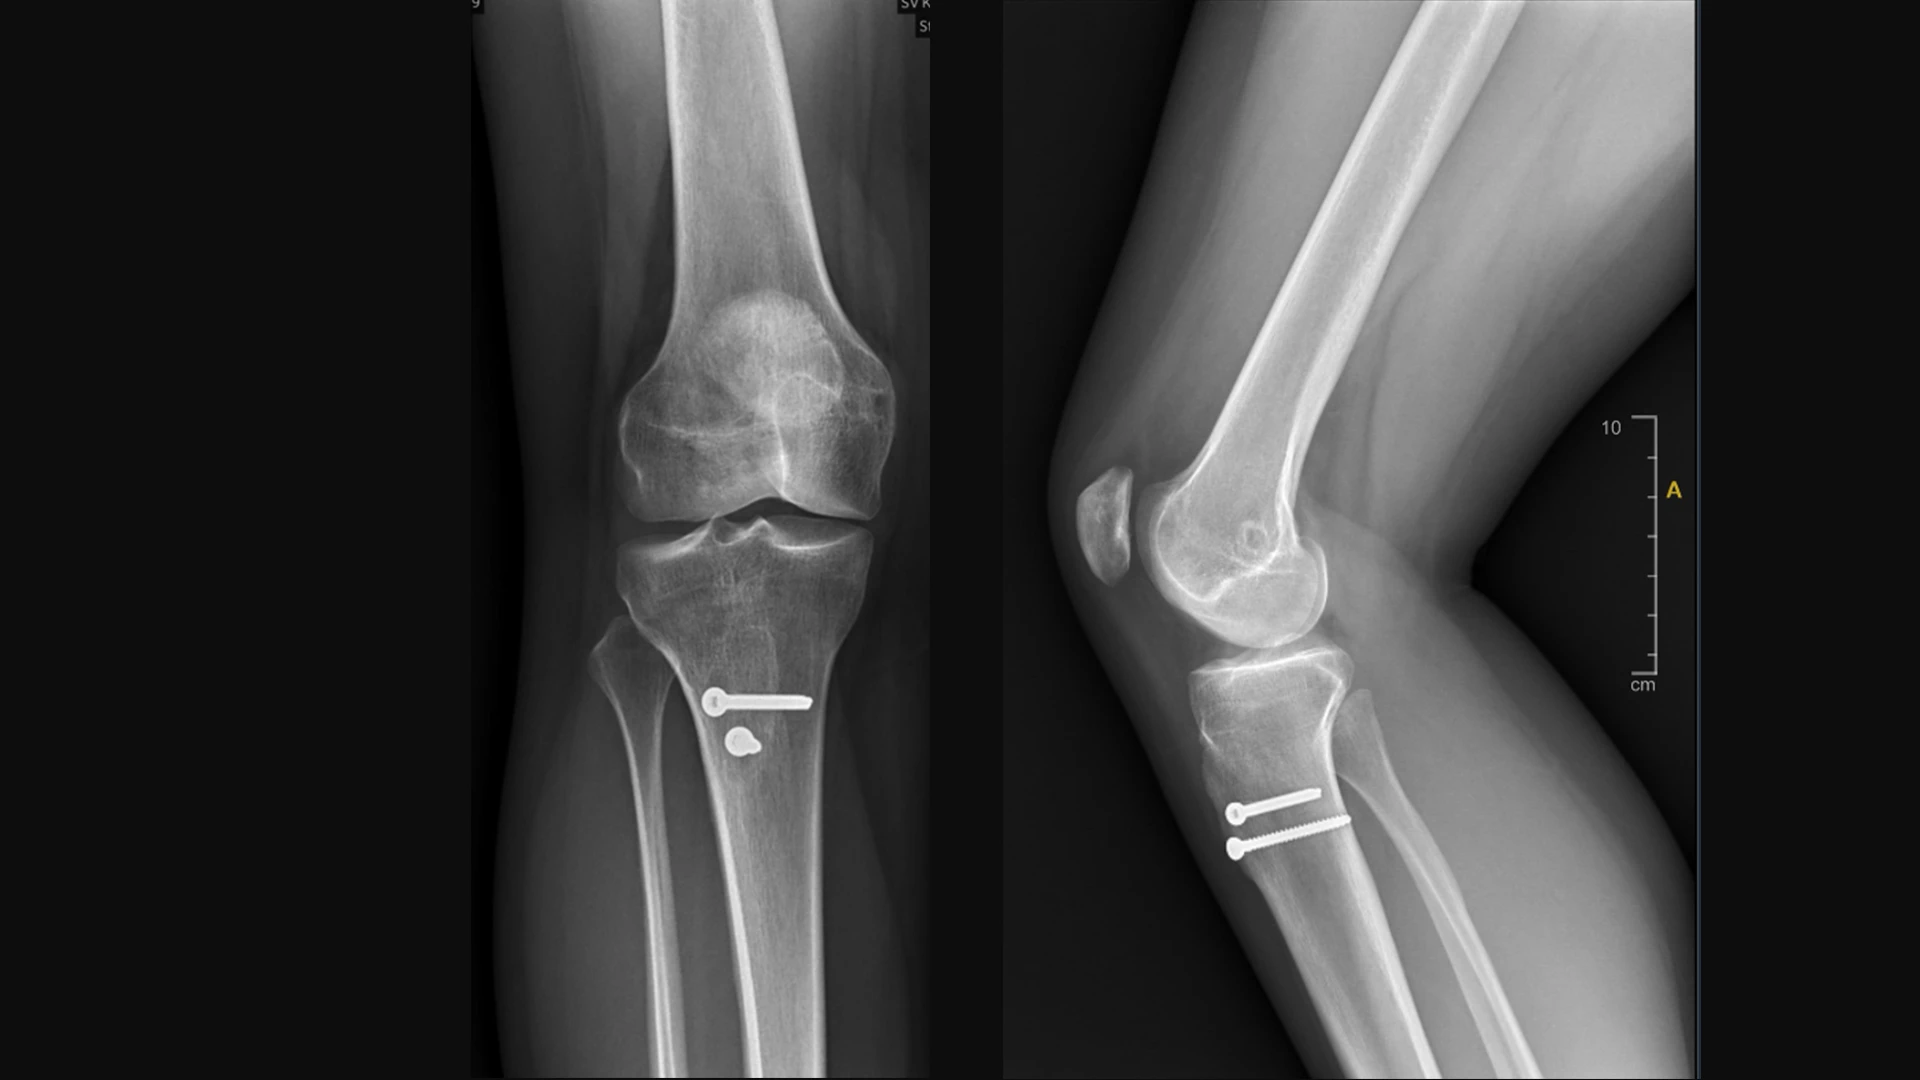

Video: A 25-year-old female patient with recurrent patellar instability and patella alta. Patient underwent a distalizing and anterior medializing tibial tubercle osteotomy and MPFL reconstruction.

Patient’s preoperative exam under anesthesia (left) depicting significant patellar translation and the inability of the patella to engage the trochlea until approximately 90 degrees of knee flexion. Patient six weeks postop during physical therapy (right) performing a straight leg raise and knee range of motion.

Anterior, posterior, and lateral view of the distalizing and anterior medializing tibial tubercle osteotomy and MPFL reconstruction.